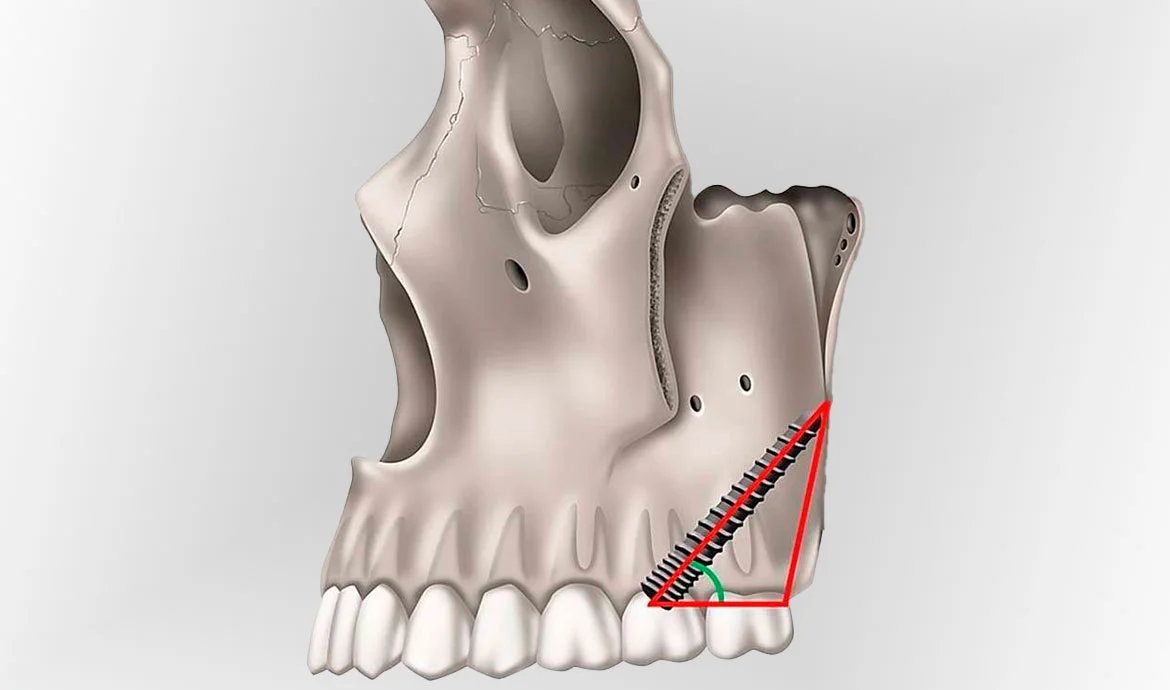

- These implants are longer than conventional ones and are placed at a precise 45–60° angle, starting in the maxillary tuberosity (the back part of the upper jaw) and anchored into the medial pterygoid plate of the sphenoid bone—a dense and stable bone that does not typically deteriorate with tooth loss.

- The implants are typically inserted at a posterior, upward, and medial angle (45–60 degrees) to bypass the maxillary sinus and directly engage with the stable pterygoid bone structure. This placement avoids the complications and healing delays associated with sinus lift surgery or bone grafting procedures.

- Angulation and Positioning: The implant is positioned at a 45-degree angle, entering the maxillary tuberosity, and then directed towards the pterygoid plate, between the sphenoid and palatine bones. This requires precision in avoiding adjacent anatomical structures such as nerves and arteries.

- Pathway for Implant: The implant must navigate through this process in a specific direction, entering from the maxillary tuberosity and angling towards the pterygoid plate, ensuring proper alignment and stability.